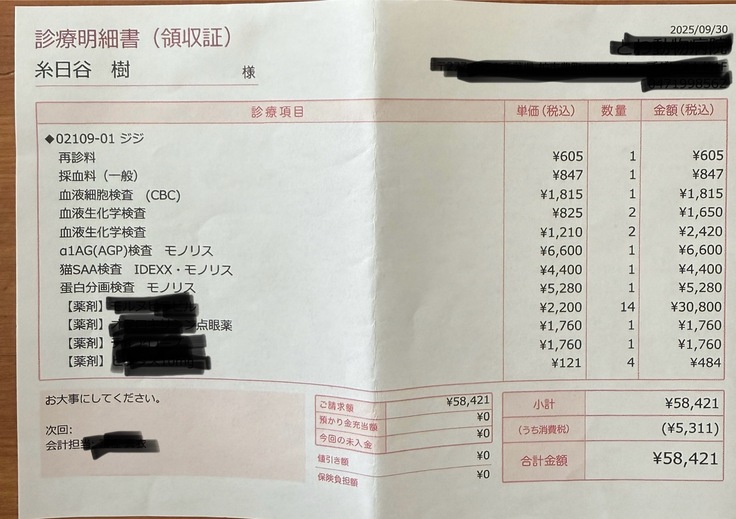

⬇️投薬7日目(9/30)

投薬を始めて1週間なので受診日でした。

検査をし、ありがたいことに検査結果は良好で腎臓や黄疸の値もものすごく下がっていました。

しかしまだ油断できる状態ではないと先生から言われ、少し安心してしまっていた自分がいたのも確かだったので、もっと気を引き締めないといけないと実感しました。

現時点までの治療費です⬇️

診察代、検査代、薬代の合計で210.386円

9/30▶️58.421円